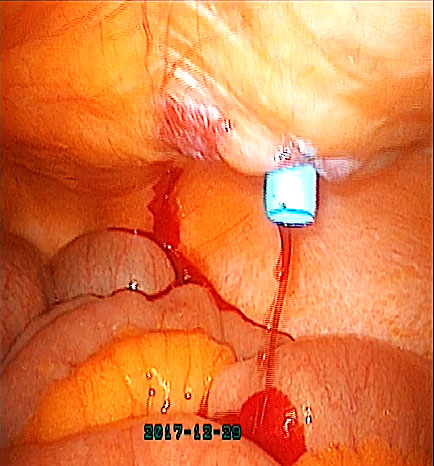

2) Clipping the uterine artery. This should be undertaken early during surgery, either at the origin of the uterine artery (Figure 9) or near its uterine insertion, while carefully safeguarding the ureter. The use of a temporary vascular loop or 'shoelace' technique, which is removed at the end of the procedure, can further assist in minimizing blood loss.13

9

Uterine artery clipped at the origin.